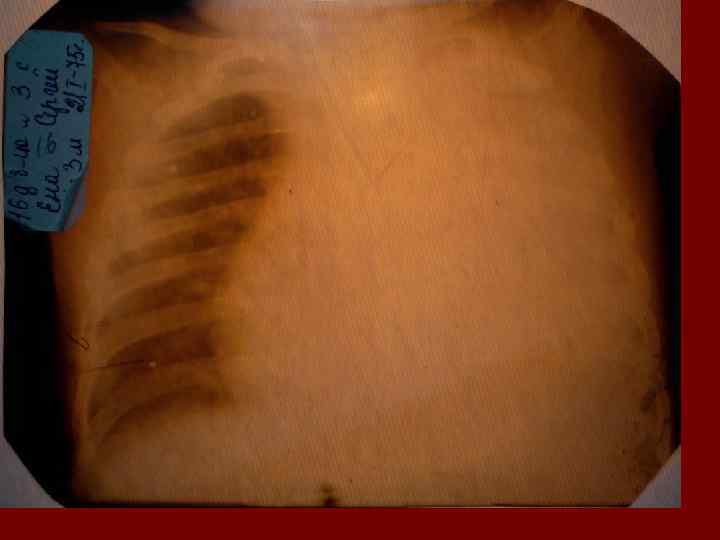

Долевая пневмония характеризуется лобарным пневмоническим инфильтратом. Крупозная ( пневмококковая) пневмония диагностируется прежде всего по клиническим данным. Крупозная пневмония сохраняет свою типичную картину пневмококковой пневмонии: острое начало с характерными клиническими данными, циклическое течение, несклонность к деструкции, гомогенной и лобарной инфильтративной тенью при рентгенологическом исследовании. Вместе с тем, широкое использование антибиотиков способствовало значительному снижению числа крупозных пневмоний у детей. Интерстициальная – редкая форма пневмоний, при которой оказывается поражен прежде всего интерстиций. Как правило, интерстициальная пневмония обусловлена вирусами, пневмоцистами, внутриклеточными микроорганизмами и грибами.

Морфологическую форму пневмонии определяют по клинико – рентгенологическим данным: выделяют очаговую, очагово – сливную, долевую ( крупозную), сегментарную и интерстициальную пневмонии. Очаговая – наиболее распространенная форма. Пневмонические очаги чаще бывают размером 1 см и более. Очагово – сливная – инфильтративные изменения в нескольких сегментах или во всей доле легкого, на фоне которых могут быть видны более плотные участки инфильтрации и/или полости деструкции. Сегментарная – в процесс вовлекается весь сегмент, который, как правило, находится в состоянии гиповентиляции, ателектаза. Морфологическая картина воспаления при очаговых и сегментарных пневмониях связана с первичным инфекционным воспалением в бронхах, что дает основание отнести эти варианты поражения легочной ткани к бронхопневмониям, нередко сопровождающихся бронхообструктивным или бронхообтурационным синдромами. В настоящее время данный тип пневмоний у детей встречается наиболее часто.